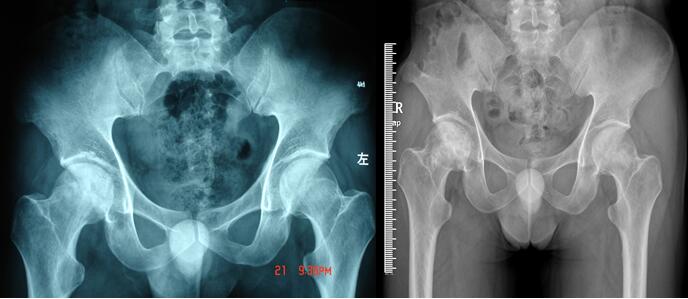

微创病灶清除陶瓷棒植入诱导血管重建治疗股骨头坏死,图为术前术后照片。